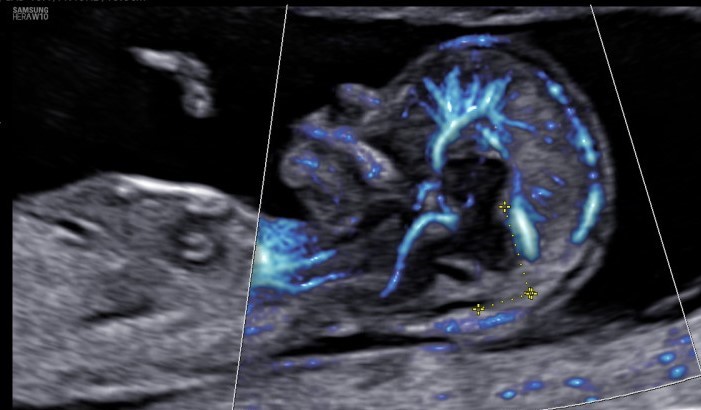

El curso pretende aportar una visión global y una puesta al día de aquellos conceptos relacionados con el diagnóstico prenatal ecográfico de los defectos estructurales y del crecimiento fetal normal y patológico desde la evidencia científica más actual.

Profundizaremos en diferentes aspectos de la ecografía morfológica fetal, del crecimiento fetal y de su relación con la disfunción placentaria siempre desde un punto de vista muy práctico utilizando una base teórica, casos clínicos reales y exploraciones comentadas.

12- Evaluación doppler materno-fetal.

Marta Claramonte / Nimet Caner